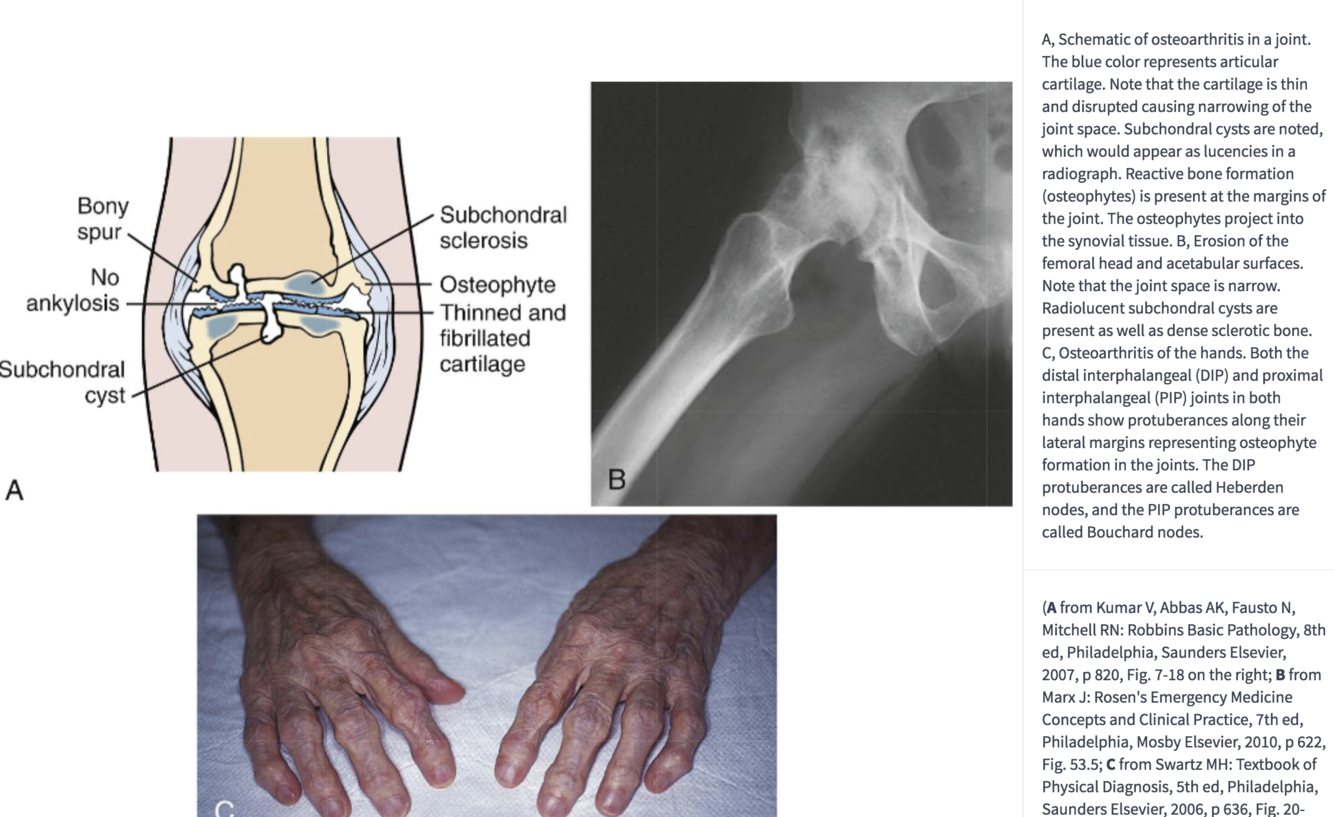

c.Joint findings

(1) Erosion and clefts in articular cartilage

(2) Reactive bone formation occurs at the joint margins (osteophytes)

OA: osteophytes at joint margins

(3) Subchondral cysts

OA: clefts, subchondral cysts

(4) Bone eventually rubs on bone.

•This produces dense, sclerotic bone.

(5) No ankylosis (fusion) of the joint

OA: no joint fusion